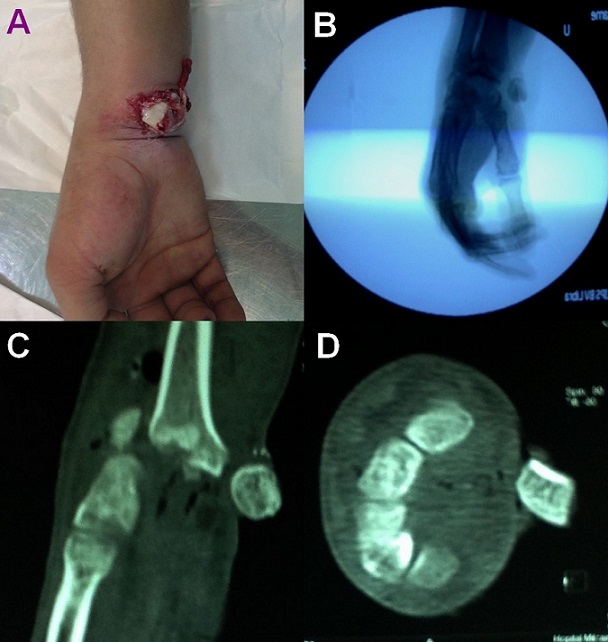

A 32 year old man, right-handed soldier, was admitted to Emergency Department two hours after undergoing right wrist injury following a 2 meter fall onto the hand, in hyperextension. Clinical examination revealed a deformity of the wrist with an obvious open lunate enucleation (A). The neurovascular status was intact. Standard radiograph of the wrist demonstrated a completely enucleated lunate, associated with scaphoid and radial styloid fracture (B). Computed tomography (CT) scan confirmed diagnosis of trans-radial styloid, trans-scaphoid, perilunate dislocation (C and D). The lunate enucleation was treated by open reduction through a volar approach and internal fixation of associated injuries. Wrist reduction was maintained using K-wires placed through the scapholunate and scaphocapitate. The material was removed after 3 months. The control during one year postoperatively, there was no evidence of complications. The patient had a comfortable range of motion in his right wrist.